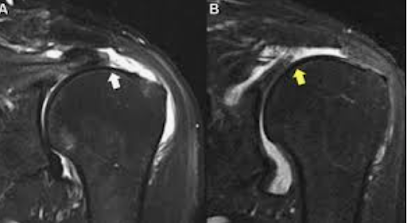

By definition, chronic, minimally traumatic cuff tears occur in tendons of inferior quality so that attempts at surgical repair are less likely to be as successful in contrast to the acute, traumatic tear. In considering the prospect of surgical repair, the surgeon and the patient should be aware of Harrison McLaughlin's admonition from 1951, "The wise surgeon, realizing that he may find little but rotten cloth to sew, will operate only by necessity and make a carefully guarded prognosis". Thus the surgeon and the patient need to know the likelihood of a successful outcome before attempting a repair for a chronic rotator cuff defect. The best prognosis for a durable repair is for tendons with only small amounts of tendon retraction away from the normal attachment on the greater tuberosity as seen on an MRI (below left - moderate retraction, below right - severe retraction)

and with minimal degeneration of the quality of the cuff tendon and muscle as seen on the MRI. Cuff tendon degeneration and fatty degeneration of the cuff muscles are correlated with patient age, tear chronicity, and size of the cuff defect.